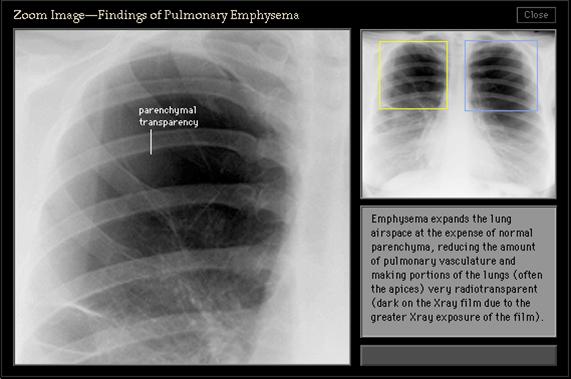

照片名称:废气中局部放大